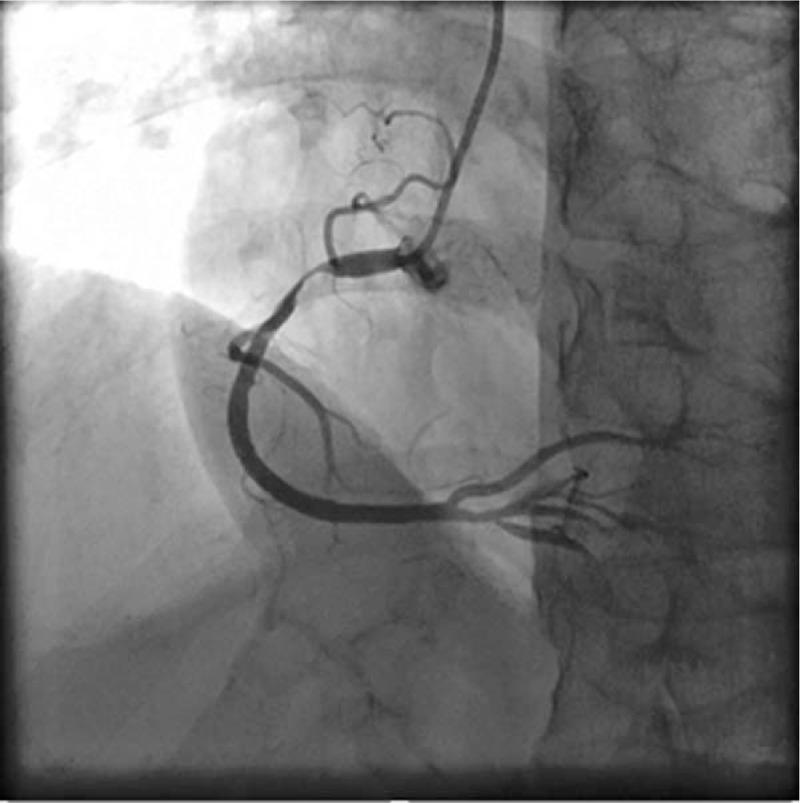

This patient received secondary preventative therapy for coronary heart disease (CHD) in combination with percutaneous transluminal coronary angioplasty (PTCA) and implantation of NeoVas Bioresorbable Coronary Scaffold.

It was thus concluded that percutaneous coronary intervention (PCI) is effective for APS patients and NeoVas scaffold implantation is presumed safe.